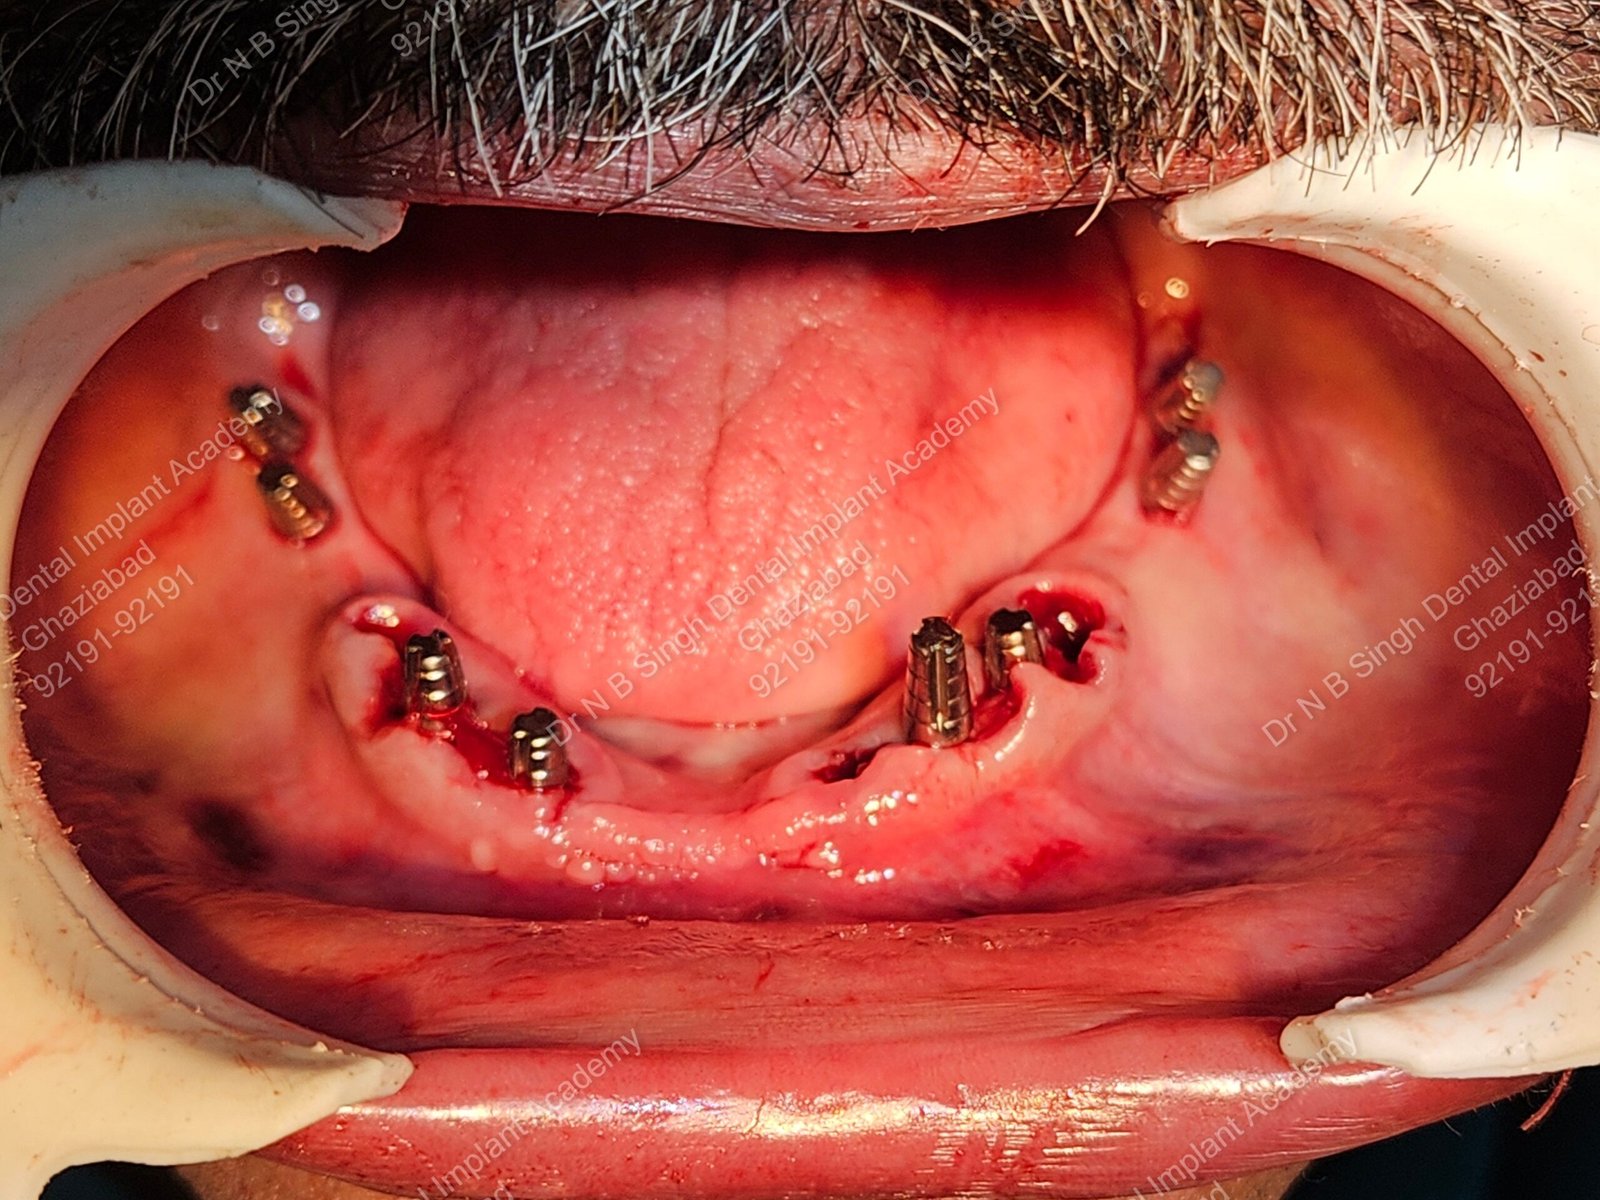

1006 Basal implant full mouth-DEEPAK